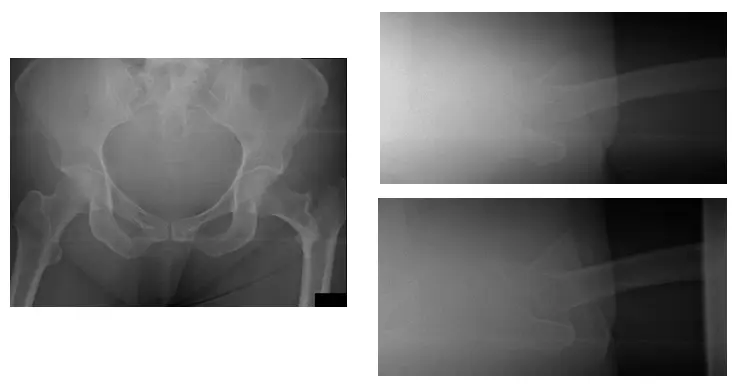

X-Rays show comminuted intertrochanteric fracture of the left hip

X-Rays show left hip post-operative of Open Reduction Internal Fixation (ORIF)